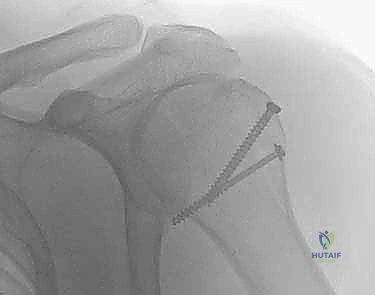

2. التثبيت بالمسامير النخاعية (Intramedullary Nailing)

في بعض كسور الرقبة الجراحية المحددة (كسور الجزأين)، يمكن استخدام مسمار نخاعي يتم إدخاله داخل تجويف العظم. يتميز هذا الإجراء بكونه طفيف التوغل (شقوق جراحية صغيرة جداً)، مما يقلل من النزيف ويحافظ على الأنسجة الرخوة والتروية الدموية.